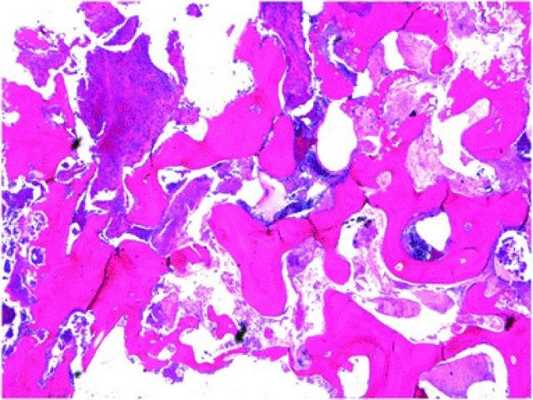

В ходе гистопатологического исследования резецированного участка нижней челюсти было обнаружено потерю остеоцитов и остеобластов в структуре ткани и заполнение костных полостей грибковой массой, а также инфильтрацию области поражения воспалительными клетками с присутствующими признаками фиброза в кости (фото 5).

Фото 5. Гистологический вид резецированного участка нижней челюсти (окраска гематоксилин-эозином).